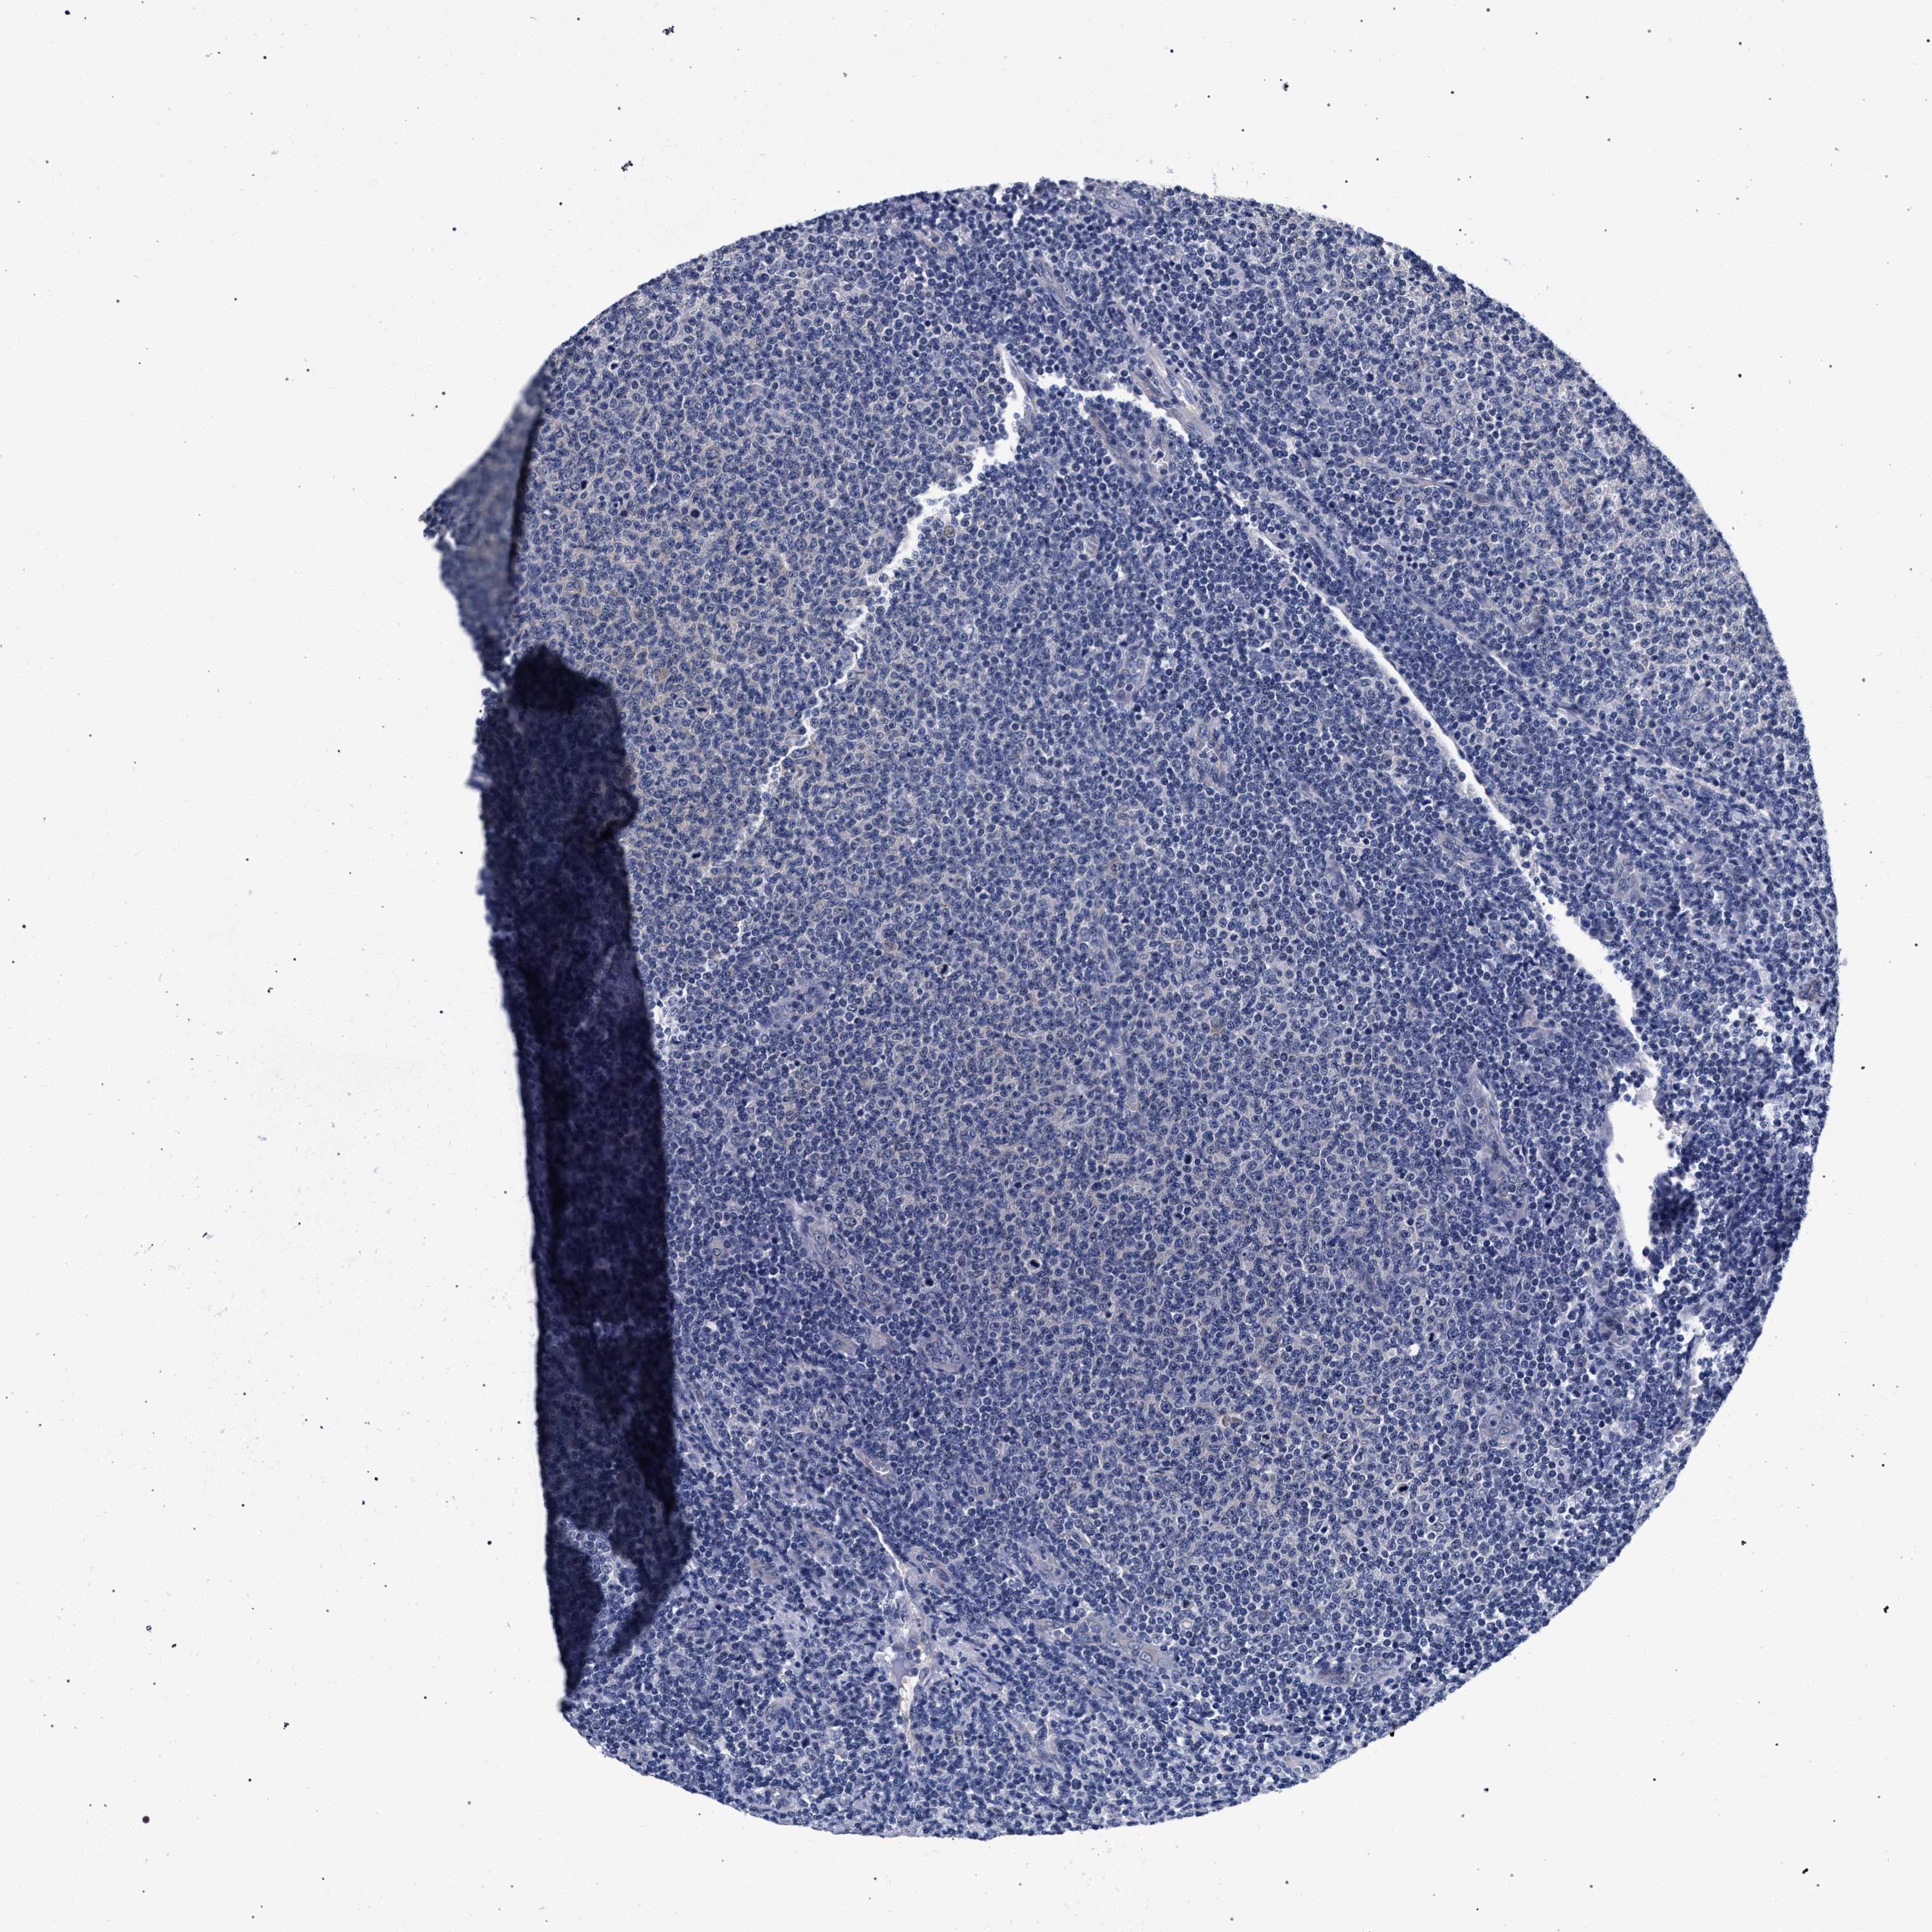

LYMPHOMA - Protein expressioni

A mouse-over function shows sample information and annotation data. Click on an image to view it in a full screen mode. Samples can be filtered based on level of antibody staining by selecting one or several of the following categories: high, medium, low and not detected. The assay and annotation is described here.

Each image is clickable and will lead to virtual microscopy that enables deeper exploration of all samples and also displays staining intensity scores, fraction scores and subcellular localization as well as patient and tissue information for each sample.

Antibody HPA019232

Hodgkin's disease, NOS

Malignant lymphoma, non-Hodgkin's type, High grade

Malignant lymphoma, non-Hodgkin's type, Low grade